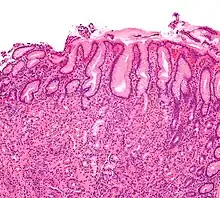

| Micrograph showing gastritis. H&E stain. | |